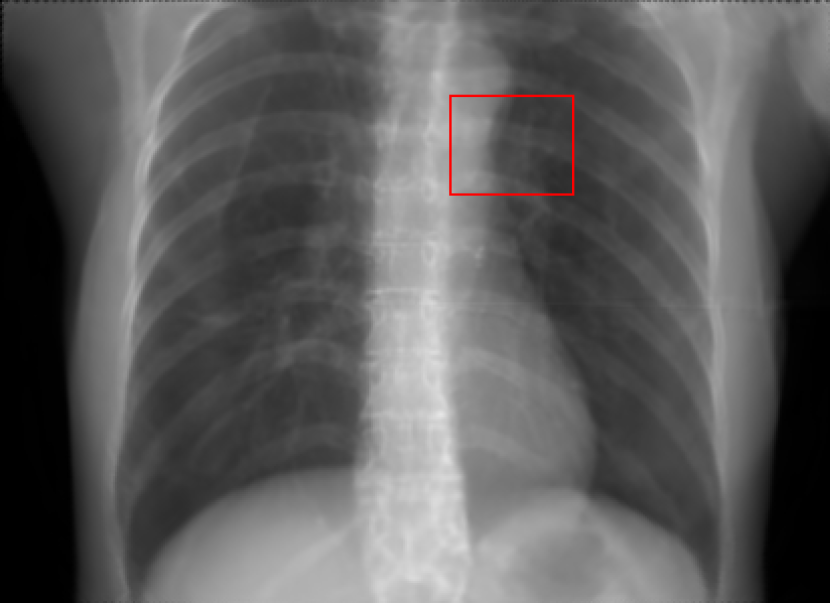

5.2 Head Data

Refer to caption

(a) Reference

(b) 0superscript00^{\circ} perspective

(c) (b)-(a)

7.80, 0.9093

Pix2pixGAN Prediction

(d) 0superscript00^{\circ} Cartesian

(e) 0&180superscript0superscript1800^{\circ}\&180^{\circ} Cartesian

(f) 0&180superscript0superscript1800^{\circ}\&180^{\circ} polar

6.06, 0.9249

2.99, 0.9820

2.07, 0.9842

Pix2pixGAN difference

(g) (d)-(a)

(h) (e)-(a)

(i) (f)-(a)

TransU-Net Prediction

(j) 0superscript00^{\circ} Cartesian

(k) 0&180superscript0superscript1800^{\circ}\&180^{\circ} Cartesian

(l) 0&180superscript0superscript1800^{\circ}\&180^{\circ} polar

6.45, 0.9356

2.36, 0.9864

3.65, 0.9734

TransU-Net Difference

(m) (j)-(a)

(n) (k)-(a)

(o) (l)-(a)

Figure 11: Perspective deformation learning in one exemplary patient case for cephalometric imaging. In (b), the left and right sides of the mandible do not overlap well, as indicated by the arrow. In (c), a scale bar of 2 mm is displayed (zoom in for better visualization), as 2 mm is the clinically acceptable precision for cephalometric landmark detection. In (e), (h) and (j), incorrect areas are marked by the red arrows.

The results of one exemplary patient for cephalometric imaging are displayed in Fig. 11. In the 0superscript00^{\circ} perspective projection image (Fig. 11(b)), because of perspective deformation, anatomical structures from the left and right sides do not overlap well, especially for the mandible as indicated by the red arrow in Fig. 11(b). It causes inaccuracy in determining the cephalometric landmark of the gonion. The difference of Fig. 11(b) to the reference Fig. 11(a) is displayed in Fig. 11(c). A scale bar of 2 mm is displayed in Fig. 11(c), as 2 mm is the clinically acceptable precision for cephalometric landmark detection. It is obvious that many anatomical structures in the 0superscript00^{\circ} perspective projection images have position shifts larger than 2 mm. In the prediction image (Fig. 11(d)) using a single 0superscript00^{\circ} view in Cartesian coordinates, perspective deformation is reduced to some degree, as displayed in the difference image Fig. 11(g). For example, the mandible region has less error. However, Fig. 11(g) also indicates that many bony structures still have deviations larger than 2 mm. The results of learning from dual complementary views in Cartesian and polar coordinates are displayed in Fig. 11(e) and Fig. 11(f), respectively. Both images have little perspective deformation, as revealed by their difference images in Fig. 11(h) and Fig. 11(i). Nevertheless, in Fig. 11(e), two dark regions are indicated by the two arrows, which are better visualized in the difference image Fig. 11(h). The results of TransU-Net are displayed in Figs. 11(j)-(o). In Fig. 11(m), the structures near the porion landmark are distorted, for example, the ear canal indicated by the arrow. Consistent with Pix2pixGAN, perspective deformation is largely reduced in the both TransU-Net prediction images using dual complementary views in Cartesian and polar coordinates.